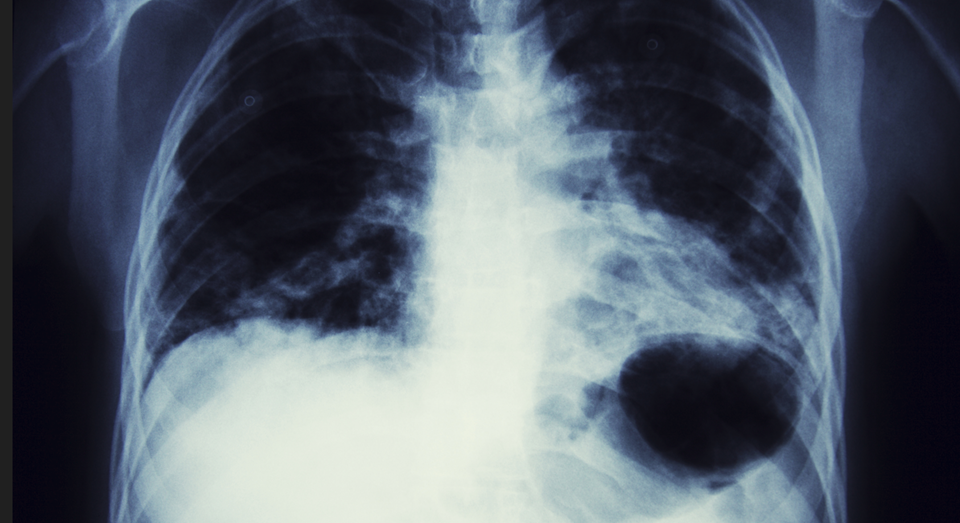

Kreftsyke mus responderte svært godt på medisinen. Musen til høyre er ubehandlet, mens den til venstre er scannet 30 dager etter behandling. Forskjellen på de to svulstene er betydelig. Figur: SINTEF